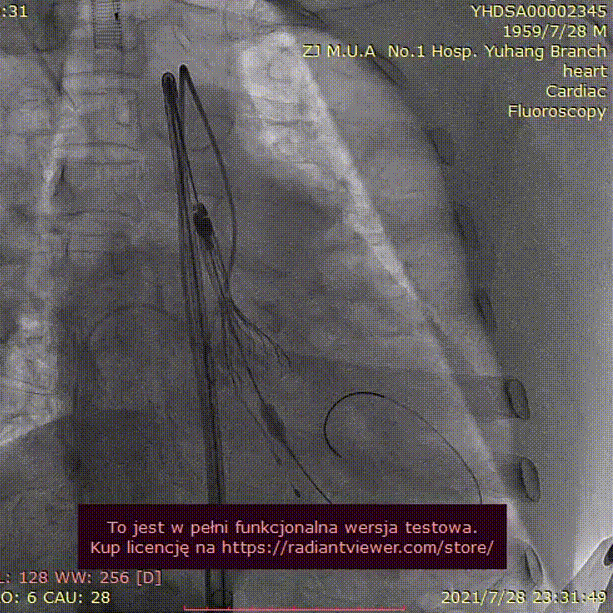

手术过程:

23mm球囊预扩

(有腰征,无返流)

开始释放后再次定位

23mm球囊后扩

植入后造影

术后压差1mmHg

术中经食道心超评估:

人工主动脉瓣:植入深度 7mm,峰值流速1.2m/s,峰值压差6mmHg,平均跨瓣压差3mmHg,原左-右冠窦结合部微量瓣周漏。